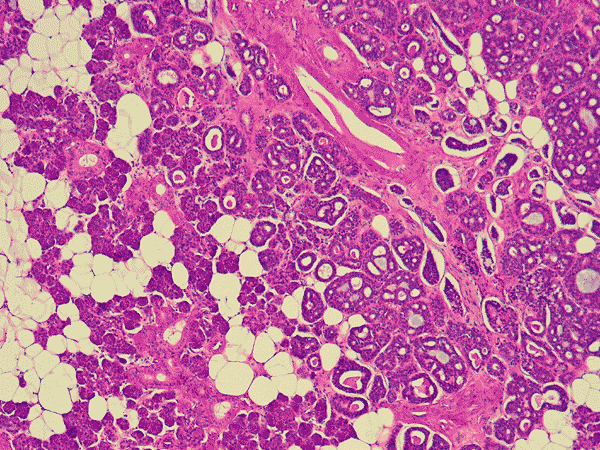

Panel A is a low-magnification photo taken at the edge of the tumor that shows tumor invasion into the surrounding salivary gland tissue. Well formed cribiform arrangment by tumor cells are show in panel B, C, and D; a fibrous stroma can be well appreciated in these photographs. Eosinophilic basement membrane like material can be well recognized in panel E; mucoid material containing microcysts are well illustrated in panel D and F. The myoepithelial component are recognized by strong immunoreactivity for calponin and smooth muscle actin (SMA) in panel G an H; note that the luminal epithelial cells do not have such immunoreactivity. Strong immunoreactivity of the tumor cells for pancytokeratin are well demonstrated in panel I

The histologic features are well illustrated in this case. In general, ADCC is a malignant tumor that is clearly invasive at macroscopic and microscopic levels. Grossly, they are usually fibrous mass with invasion into the surrounding tissue. The stroma of ADCC is typically fibrotic. The common histologic patterns are the cribiform pattern, tubular pattern and solid pattern. The less common pattern are the spindle cell pattern, trabecular pattern and solid type with comedo-type necrosis. Common histologic features are cribriform or microcystic architecture with relatively uniform cells, with small, hyperchromatic nuclei, scant cytoplasm, somewhat nulcear molding and indistinct cytoplasmic border. These cells are considered as myoepithelial differentiation.  A second cell type can be recognized as somewhat larger, with more abundant cytoplasm and less dense nuclear chromatin. These cells are thought to represent ductal epithelial cells. The ductal cells give rise to real tubular structures that contain bluish mucoid material; these cells are immunoreactive for carcinoembryonic antigen (CEA), epithelial membrane antige  (EMA), keratin, and S-100 protein. The myoepithelial cells may arrange in solid sheets and also give rise to microscystic structures containing hyalinized eosinophilic basement membrane-like material. They bear immunoreactivity for calponin, muscle specific actin, and low molecular weight cytokeratin. They are also positive for S-100 protein but are usually less strong than the ductal cells in the same tumor. Many ADCC also express C-kit (CD117) 2, especially in solid type. PAS (+) basement membrane-like material is seen in the pseudocyts and mucin in the true ducts. Perineural invasion is the rule. The tumor cells are highly proliferative and a Ki-67 labeling index over 20% is not uncommon.